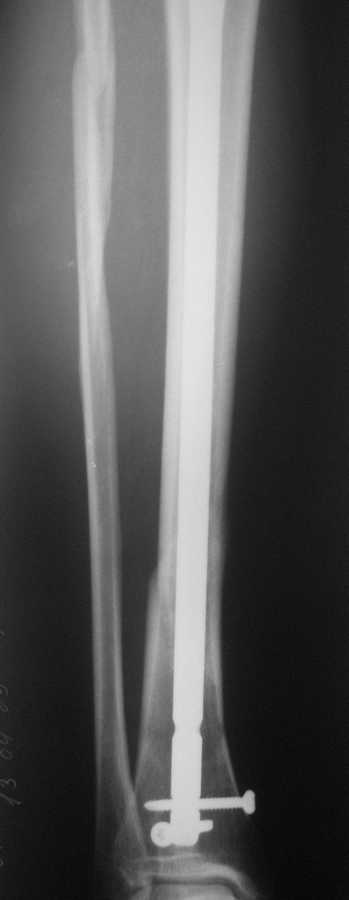

В январе 2009 года нами оперирована пациентка с переломом н\3 голени штифтом Expert. Динамизация через 4 месяца, пациентка при этом уже ходила с тростью. Дома периодически передвигалась без дополнительной опоры.

В настоящее время - через 9 месяцев с момента операции периодически в вечернее время беспокоят ноющие боли в места перелома (не постоянно). При беседе выяснено, что боли чаще беспокоят после того, как днем она походит по дому без трости. Пальпаторно по гребню берцовой кости болей нет, но по задне-внутренней поверхности б\б кости пальпирутеся западение на уровне места перелома.

Имя     : через 9 месяцев (3).jpg

Тип     : image/jpeg

Размер  : 79268 байтов

Описание: отсутствует

Url     : http://weborto.net:8080/pipermail/ortho/attachments/20090913/ceda924c/attachment-0005.jpg